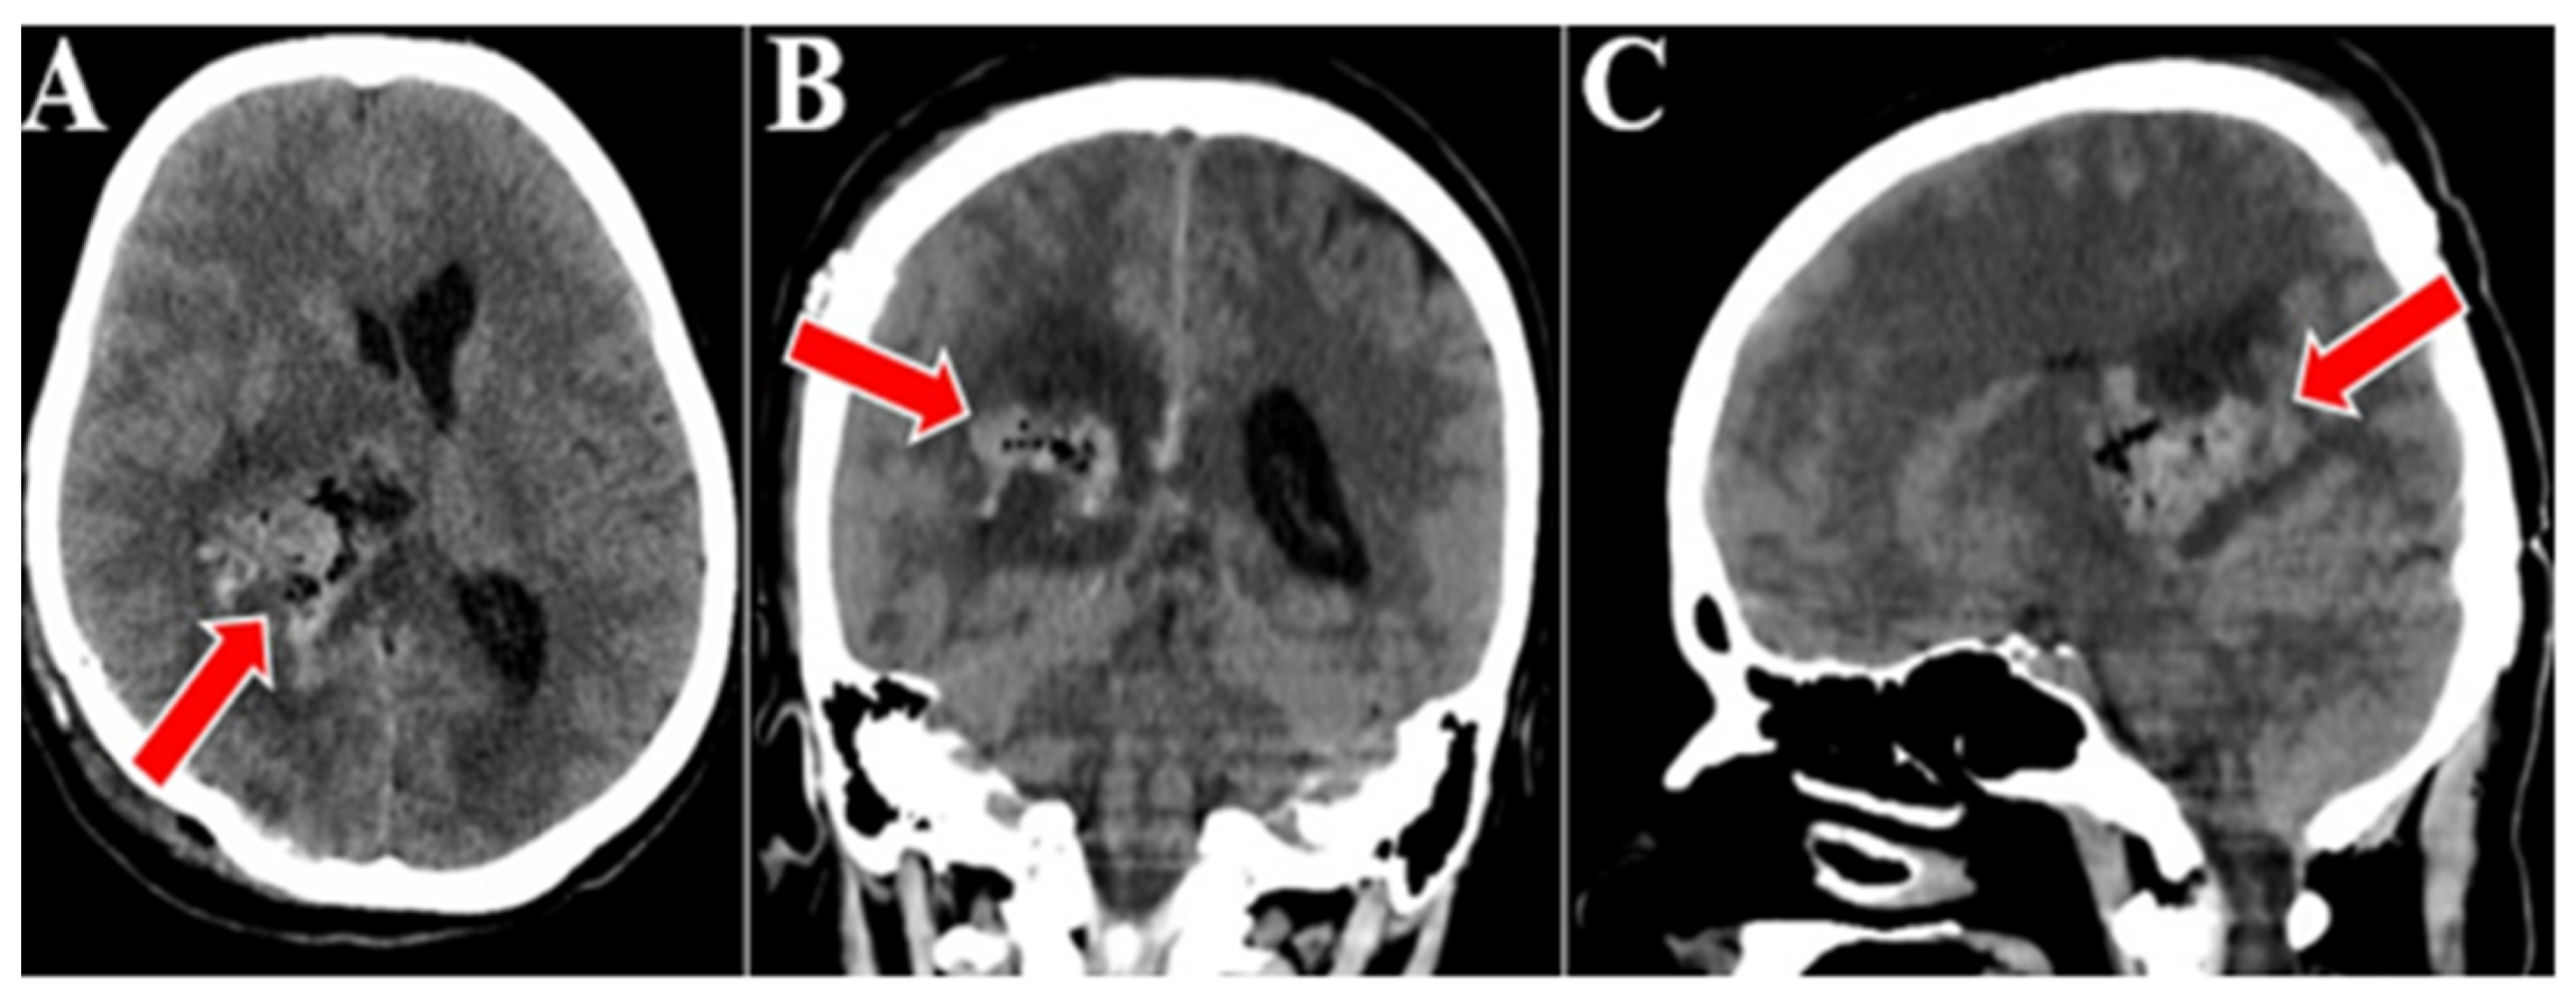

2. Case Presentation